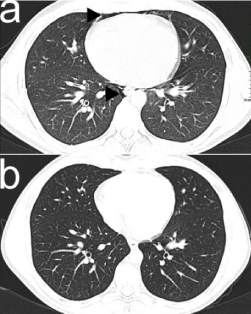

Chest X-ray (CXR) revealed clear lung fields, pneumomediastinum (PM) and emphysema in the soft tissues between the muscles of the neck (Figure 1a). Pulmonary computed tomography (CT) without contrast showed pneumomediastinum (PM), i.e. air dissecting tissue planes extending in the soft tissues of the neck, including the muscles, the nerves, the right rear second back rib and the ipsilateral front first and second anterior rib, all the mediastinal recesses (also anterior) and the bilateral peribronchial and paraesophageal spaces until the diaphragmatic hiatus. CT also showed a solution of continuity of the right postero-lateral portion of the trachea with adjacent minimum hypo-dense material (Figures 2a, 3a, 4a). In emergency department, the application of human fibrin glue by means of bronchoscopy was used to seal the tracheal lesion. CXR showed complete resolution of the PM and subcutaneous emphysema after 12 days (Figure 1b). Chest CT without contrast also revealed complete resolution at 15 days (Figures 2b, 3b, 4b).

Figure 2. Air dissecting into the mediastinal spaces and the cervical soft tissues (a) and complete resolution (b) on CT scan in axial plane after 15 days. CT scan was performed with Siemen's somatom sensation 16 slices, 130-217 mAs, 120 kV energy, and slice thickness was 1.5 x 1.5 mm. No contrast was used (a). The second CT scan was also performed with Siemen's somatom sensation 16 slices, 200-217 mAs, 120 kV energy, and slice thickness was 1.5 x 1.5 mm. No contrast was used (b).